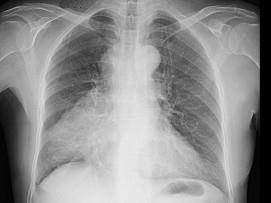

问题 男,62岁,既往有右肺腺癌史,现出现头痛、头晕、恶心、视物模糊,CT检查如图,最可能的诊断是()

选项 A.脑梗死 B.胶质瘤 C.脑膜瘤 D.畸胎瘤 E.脑转移瘤

答案 E